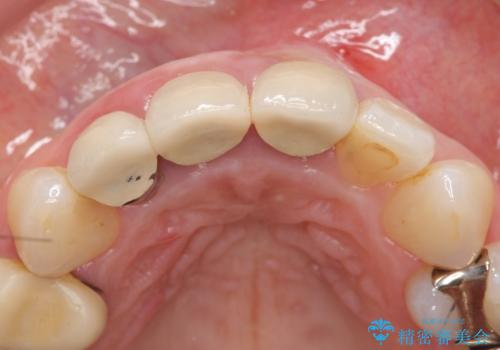

- 前歯の長さが違うのが気になるといらっしゃった方の症例です。

根尖病変を認めたため再根管治療を行った後、オールセラミッククラウン(スペシャル)にて補綴を行いました。

歯肉の腫れをより改善するため歯周外科を提案しましたが希望されませんでした。